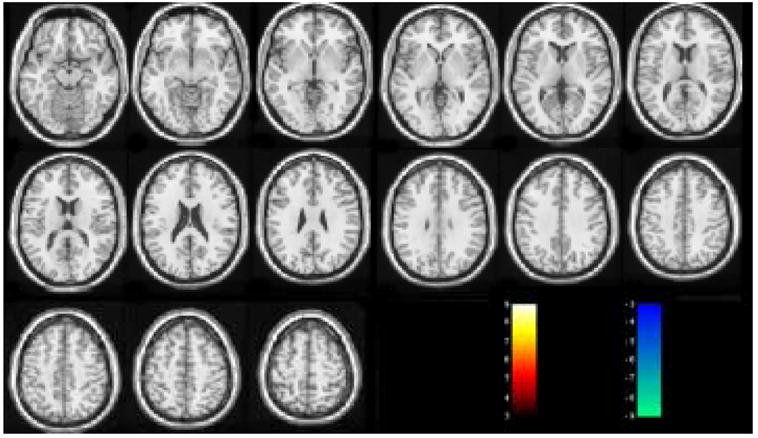

Fig. 3 and Fig. 4 are the suprathresholded t maps of GLM RFX and SDM RFX from the null hypothesis resting CBF image series. With the same threshold abs(t) > 3 (corresponding to P < 0.012), GLM RFX yielded many falsely detected activated voxels, while SDM RFX did not show any suprathresholded voxels.

Figure 3.

GLM RFX results of the null hypothesis resting CBF data. The t threshold is arbitrarily chosen to be 3.

Figure 4.

SDM RFX results of the null hypothesis resting CBF data. The t threshold is the same as in Fig. 3.

Using a null hypothesis ASL perfusion dataset, SDM RFX yielded almost no false detected voxels (Fig. 4) with a threshold P < 0.012, while GLM RFX presented many false detected activated or deactivated voxels (Fig. 4). Validations using synthetic functional data demonstrated that SDM RFX yielded higher detection sensitivity in terms of higher mean t value in the a priori regions than GLM RFX for every simulated signal change strength and any explored cluster size. As synthetic activations were injected to both neighboring and distant voxels and no smoothing was applied before GLM or SDM analysis, these results demonstrated that spatial activation coherence can be utilized by SVM based multivariate processing to improve the detection sensitivity. ROC analysis further demonstrated that SVM based individual level data analysis and group analysis (SDM RFX) yielded better performance (larger AUC) than GLM based individual level data analysis and group analysis (GLM RFX), respectively.